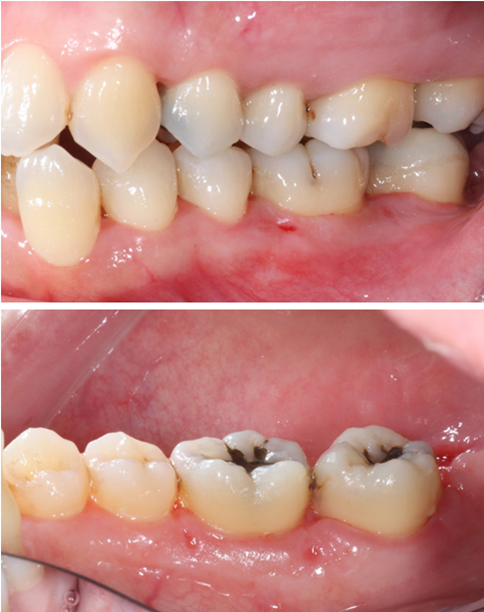

術後兩周 傷口恢復良好

右側

左側